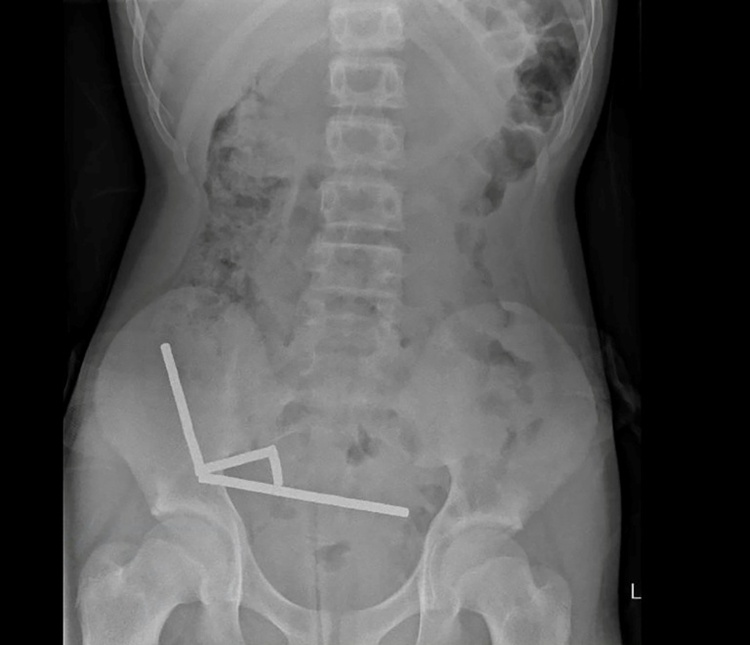

Röntgenbild zeigt die Magneten im Unterleib des 13-Jährigen Bild: AFP

Die Magneten, die in Neuseeland seit Anfang 2013 verboten seien, seien auf der Temu-Plattform gekauft worden, teilten die Ärzte mit. Eine Röntgenaufnahme habe gezeigt, dass die Magneten sich in verschiedenen Bereichen des Darms aufgrund der Anziehungskraft zu vier geraden Linien zusammenklumpten. Den Ärzten zufolge starb durch die Kraft der Magneten an vier Stellen im Dünn- und Dickdarm Gewebe ab.